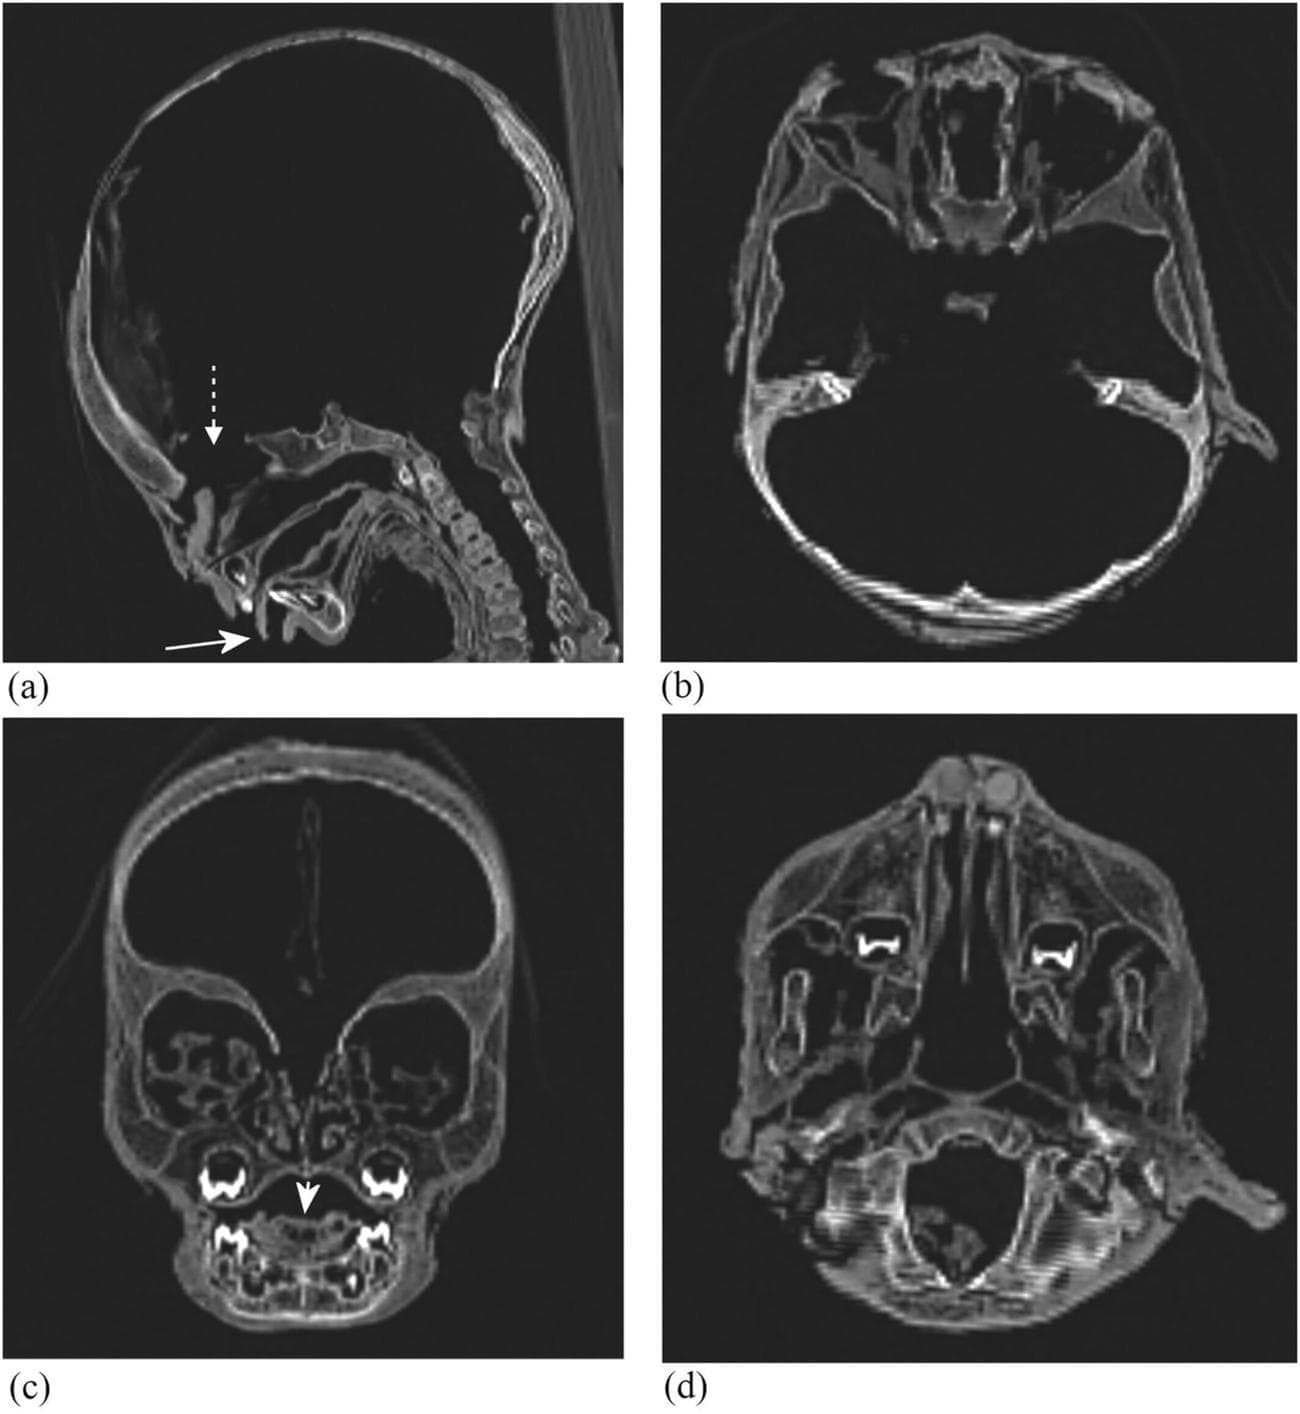

Μία διεθνής ομάδα ερευνητών μελέτησαν τις μούμιες παιδιών από την αρχαία Αίγυπτο, χρησιμοποιώντας αξονικές τομογραφίες και αποκάλυψαν πως μία συγκεκριμένη ασθένεια ήταν αρκετά κοινή εκείνη την εποχή. Μελετώντας μούμιες παιδιών από διάφορα μουσεία της Ευρώπης, διαπίστωσαν πως το 1/3 αυτών έπασχε από αναιμία.

Η μελέτη μας είναι η πρώτη που παραδίδει ραδιολογικά δεδομένα όχι μόνο από το κρανίο αλλά και από τα οστά του προσώπου.

Το κατά πόσο η αναιμία μπορεί να έπαιξε ρόλο στο θάνατο κάθε παιδιού που εξετάστηκε, δεν μπορεί να διαπιστωθεί από τις αξονικές τομογραφίες, αλλά οι επιστήμονες πιστεύουν πως σίγουρα συνέβαλε σε αυτό. Οι ερευνητές μελέτησαν τα οστά από τις μούμιες, τα οποία μπορούν να προσφέρουν αποδείξεις ύπαρξης αναιμίας, επειδή ο μυελός των οστών είναι αυτός που παράγει τα ερυθρά αιμοσφαίρια.

Η χρόνια αιμολυτική αναιμία και η αναιμία από έλλειψη σιδήρου συνήθως συνοδεύονται από μία μεγέθυνση της περιοχής του κρανίου που στεγάζει τον εγκέφαλο, ενώ υπάρχουν και δείκτες όπως αλλαγές στο σχήμα των οστών.

Η ομάδα βρήκε πως από τις 21 μούμιες παιδιών από γερμανικά, ιταλικά και ελβετικά μουσεία, οι 7 είχαν μετρήσιμα σημάδια αναιμίας. Οι μούμιες των παιδιών κυμαίνονταν σε ηλικίες από 1 έως 14 ετών όταν πέθαναν, ενώ έζησαν σε διαφορετικές χρονικές περιόδους.

Η χρονολογικά παλαιότερη μούμια φτάνει μέχρι το 2686 π.Χ., ενώ οι περισσότερες αφορούν την Πτολεμαϊκή και Ρωμαϊκή περίοδο από το 332 π.Χ. έως το 395 μ.Χ. Ο σκοπός της έρευνας ήταν να εκτιμήσουμε την επικράτηση της αναιμίας στις αρχαίες αιγυπτιακές μούμιες παιδιών και να προσφέρουμε μετρήσιμα δεδομένα για μελλοντικές μελέτες.